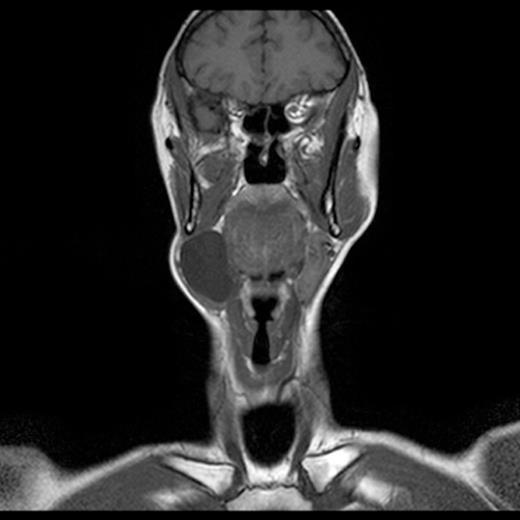

Examination of the oral cavity and oropharynx was unremarkable. Palpation of the neck mass revealed a soft, fluctuant, non-tender swelling approximately 6cm in diameter arising superficially within the right submandibular region. There was no associated cervical lymphadenopathy. A magnetic resonance imaging (MRI) scan revealed a large cystic structure in the right lateral neck involving the submandibular space (Fig 1). There was no ‘tail’ sign. No other abnormalities were demonstrated. Fine needle aspiration biopsy revealed abundant cystic fluid. The sample proved inadequate for cytological assessment, however was found to have a raised amylase and protein content suggesting salivary origin. Routine blood tests were all normal.